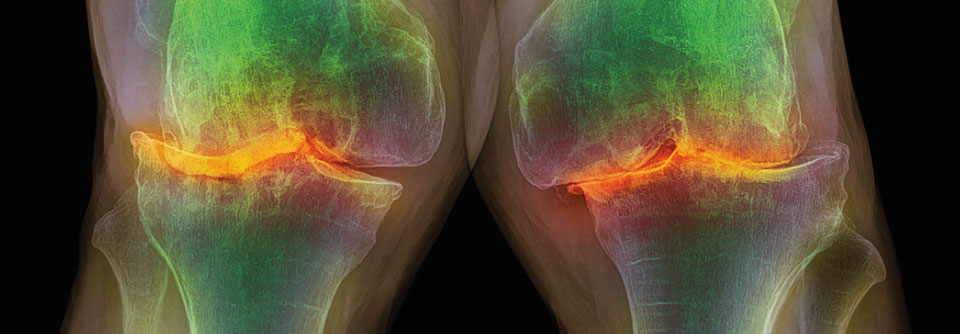

Bei Arthrosen handelt es sich um langsam progrediente, primär nicht entzündliche degenerative Erkrankungen des Gelenkknorpels und anderer Gelenkbestandteile. Zwischendurch können entzündliche Episoden mir akuten Schmerzen auftreten, was dann als „aktivierte Arthrose“ bezeichnet wird. Im Spätstadium können dann auch Dauerschmerzen und Funktionsminderungen auftreten.

Arthrosen sind die häufigste Gelenkerkrankung – die Inzidenz nimmt mit dem Alter zu. Im 6. Lebensjahrzehnt zeigen circa 20 % der Menschen im Röntgenbild eine Knie- oder Hüftgelenksarthrose – nur 20 bis 30 % haben dabei aber subjektive Beschwerden. Bei den anderen handelt es sich um eine „stille“ oder latente Arthrose, die nicht behandlungsbedüftig ist. Bis zum 80. Lebensjahr steigt die Prävalenz einer radiologischen Gonarthrose z.B. bei Männern auf 33 %, bei Frauen auf 53 % an. Nur 10 bis 15 % der Menschen mit radiologisch gesicherten Gonarthrose geben dabei aber klinische Beschwerden an.

• Arthroseanzeichen sind Gelankspaltverschmälerung, subchondrale Sklerosierung, Geröllzysten, Osteophyten

• in schweren Fällen Deformierung des Gelenkes, sekundäre Chondrokalzinose